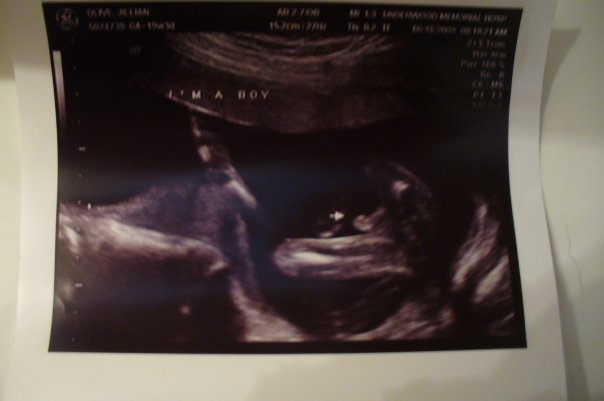

Here is a pic of my ds ultrasound. You can tell the difference from yours to mine. Image Attachment(s):

That's a girl. I am due the week before you are and this was my "money shot" from the Level 2 which was done about 2 weeks ago:

Needless to say, I am DEFINITIVELY having a boy.